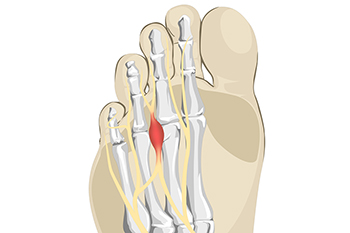

What Is a Neuroma?

The pain from a foot condition that is known as Morton’s neuroma is generally found in the ball of the foot. A neuroma is another name for a pinched nerve or nerve tumor. It is often benign, and can grow and spread to other nerves in the foot. It is an ailment that affects the nerves between the third and fourth toes, and can cause severe pain and discomfort. Many patients describe the pain as feeling like a pebble or marble under the foot, and possibly cause difficulty in completing daily activities. Common reasons for this condition to develop can include frequently wearing high heels, and participating in running and jumping activities that can compress the feet in shoes. Additionally, medical conditions consisting of bunions and hammertoes may lead to getting Morton’s neuroma. A proper diagnosis consists of having a CT scan taken, or possibly an MRI. Many people have found mild relief when specific foot stretches are performed, and it can be beneficial to wear shoes that fit correctly. These types of shoes will have adequate room for the toes to move freely in, and this can help to achieve full range of motion and flexibility. Morton’s neuroma can be painful, and can hinder the ability to complete daily tasks. If you have pain in this part of your foot, it is suggested you consult with a podiatrist who can accurately diagnose and treat Morton’s neuroma.

Morton’s neuroma is a very uncomfortable condition to live with. If you think you have Morton’s neuroma, contact one of our podiatrists of Lexington Foot and Ankle Center, PSC. Our doctors will attend to all of your foot care needs and answer any of your related questions.

Morton’s Neuroma

Morton's neuroma is a painful foot condition that commonly affects the areas between the second and third or third and fourth toe, although other areas of the foot are also susceptible. Morton’s neuroma is caused by an inflamed nerve in the foot that is being squeezed and aggravated by surrounding bones.

What Increases the Chances of Having Morton’s Neuroma?

- Ill-fitting high heels or shoes that add pressure to the toe or foot

- Jogging, running or any sport that involves constant impact to the foot

- Flat feet, bunions, and any other foot deformities

Morton’s neuroma is a very treatable condition. Orthotics and shoe inserts can often be used to alleviate the pain on the forefront of the feet. In more severe cases, corticosteroids can also be prescribed. In order to figure out the best treatment for your neuroma, it’s recommended to seek the care of a podiatrist who can diagnose your condition and provide different treatment options.